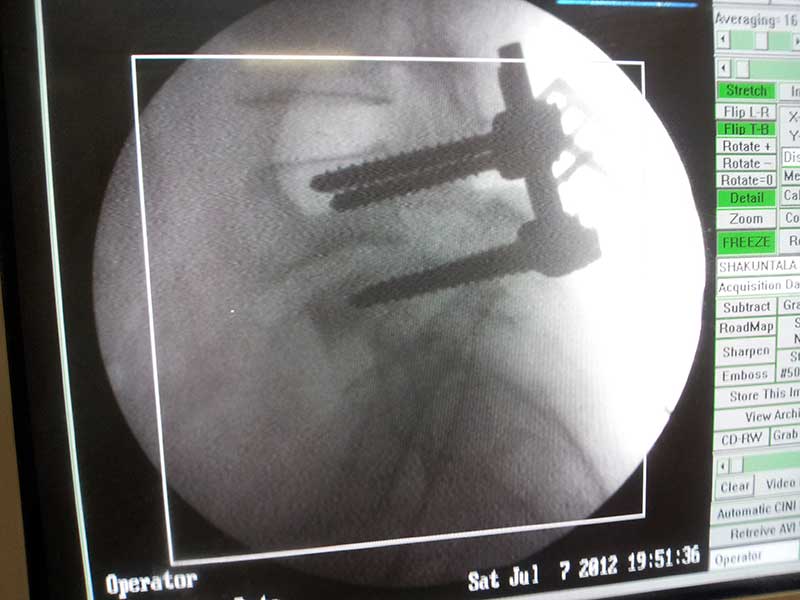

INTRA OP SPINE FIXATION

Spine Fixation Lumbar Spine

• Spine Fixation Lumbar Spine